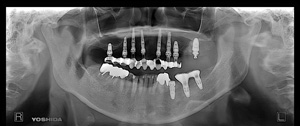

‚Q‚O‚Q‚R”N  ‚XŒŽ ‚Q‚X“úi‹àj@㉺Š{ ƒm[ƒxƒ‹ƒKƒCƒhŽg—p@Ö¬“à’ÁÕ¹—p

@@@@@@@@@ãŠ{@‚X–{@@’x‰„‰×d  IPƒCƒ“ƒvƒ‰ƒ“ƒg‚S–{•¹—p@‘OŽ••”ƒvƒƒr

@@@@@@@@@‰ºŠ{@‚S–{@  ’x‰„‰×d

@@@@@@@@@@@”‚P‚VF  Nobel Speedy Groovy@RP  ‚SD‚O ‚‚  ~ ‚P‚O ‚‚

@@@@@@@@@@@”‚P‚UF  Nobel Speedy@Sho‚’ty@RP  ‚SD‚O ‚‚  ~  ‚V ‚‚

@@@@@@@@@@@”‚P‚SF  Nobel Speedy Groovy@RP  ‚SD‚O ‚‚  ~ ‚P‚O ‚‚

@@@@@@@@@@@”‚P‚QF  Nobel Speedy Groovy@RP  ‚SD‚O ‚‚  ~ ‚P‚W ‚‚

@@@@@@@@@@@”‚Q‚PF  Nobel Speedy Groovy@RP  ‚SD‚O ‚‚  ~ ‚P‚W ‚‚

@@@@@@@@@@@”‚Q‚RF  Osstem@US2@RP  ‚SD‚O ‚‚  ~ ‚P‚T ‚‚

@@@@@@@@@@@”‚Q‚SF  Nobel Speedy@Sho‚’ty@RP  ‚SD‚O ‚‚  ~  ‚V ‚‚

@@@@@@@@@@@”‚Q‚UF  Nobel Replace Conical Connection ‚s‚h‚t‚Œ‚”‚’a@RP  ‚SD‚R ‚‚  ~ ‚W ‚‚

@@@@@@@@@@@”‚Q‚VF  Nobel Speedy Groovy@RP  ‚SD‚O ‚‚  ~ ‚P‚PD‚T ‚‚

@

@@@@@@@@@@@”‚S‚VF  Nobel Replace Conical Connection ‚s‚h‚t‚Œ‚”‚’a@RP  ‚TD‚O ‚‚  ~ ‚W ‚‚

@@@@@@@@@@@”‚S‚UF  Nobel Replace Conical Connection ‚s‚h‚t‚Œ‚”‚’a@RP  ‚TD‚O ‚‚  ~ ‚W ‚‚

@@@@@@@@@@@”‚R‚UF  Nobel Replace Conical Connection ‚s‚h‚t‚Œ‚”‚’a@RP  ‚SD‚R ‚‚  ~ ‚W ‚‚

@@@@@@@@@@@”‚R‚UF  Nobel Replace Conical Connection ‚s‚h‚t‚Œ‚”‚’a@‚mP  ‚RD‚T ‚‚  ~ ‚W ‚‚